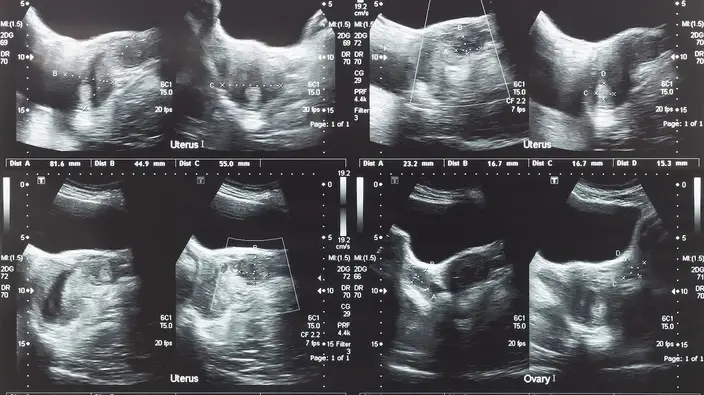

- آزمایشات تصویربرداری: سونوگرافی معمولا به عنوان یک روش تصویربرداری ابتدایی برای تشخیص فیبروم رحم استفاده میشود. این روش امکان مشاهدهٔ تودههای رحمی را فراهم میکند و به پزشک کمک میکند تا اندازه، تعداد و موقعیت فیبرومها را بررسی کند. در مواردی که سونوگرافی کافی نباشد، ممکن است از روشهای دیگر مانند MRI استفاده شود.